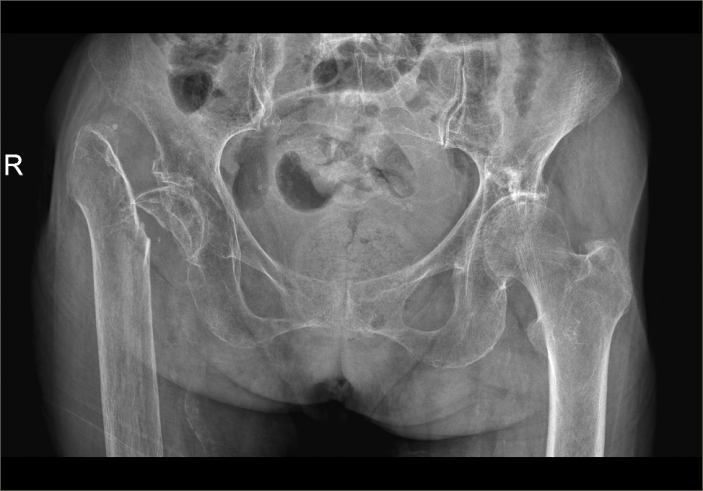

△骨科于15日、16日收治的另外兩位高齡患者

△術前

△術後